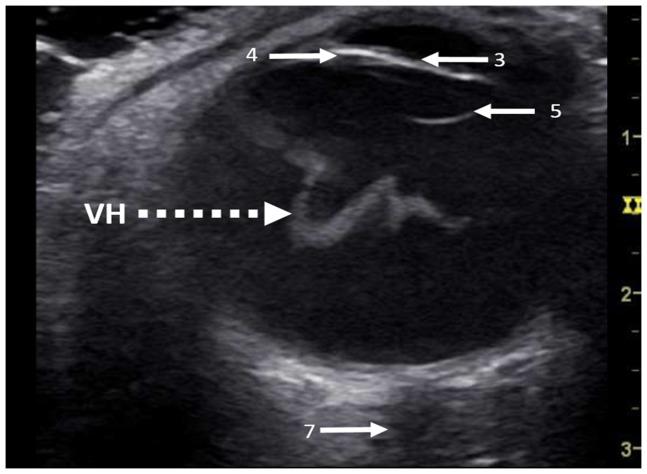

Intraocular hemorrhage in patients suffering from aneurysmal subarachnoid hemorrhage is known as Terson's syndrome and is an underestimated but common pathology. We therefore designed a prospective single-blinded study to evaluate the validity of ocular ultrasound compared to the gold standard indirect funduscopy in the diagnosis of Terson's syndrome.

Fifty-two patients (104 eyes in total) suffering from aneurysmal subarachnoid hemorrhage were enrolled in this study. Two investigators independently performed a single-blinded ocular ultrasound using a standard intensive care ultrasound system to detect an intraocular hemorrhage. Indirect funduscopy following iatrogenic mydriasis served as the gold standard for confirmation or exclusion of an intraocular hemorrhage. Statistical analyses were performed to evaluate the sensitivity and specificity, positive and negative predictive values of the method as well as the learning curve of ocular ultrasound.

Indirect funduscopy detected Terson's syndrome in 11 of 52 (21.2%) respectively in 21 of 104 (20.2%) eyes in patients suffering from subarachnoid hemorrhage. Sensitivity and specificity increased with the number of ocular ultrasound examinations for both investigators, reaching 81.8% and 100% respectively. Positive and negative predictive values were different for both investigators (63.6% vs. 100% positive and 100% vs. 95.7% negative) but were both correlated to the amount of intraocular hemorrhage. A low Glasgow Coma scale (p = 0.015) and high Hunt & Hess grade (p = 0.003) was associated with a higher rate of Terson's syndrome.

Ocular ultrasound using standard ultrasound equipment has been confirmed as a reliable, easy-to-handle bedside screening tool for detecting Terson's syndrome. Nevertheless funduscopy remains the gold standard to detect Terson's syndrome.